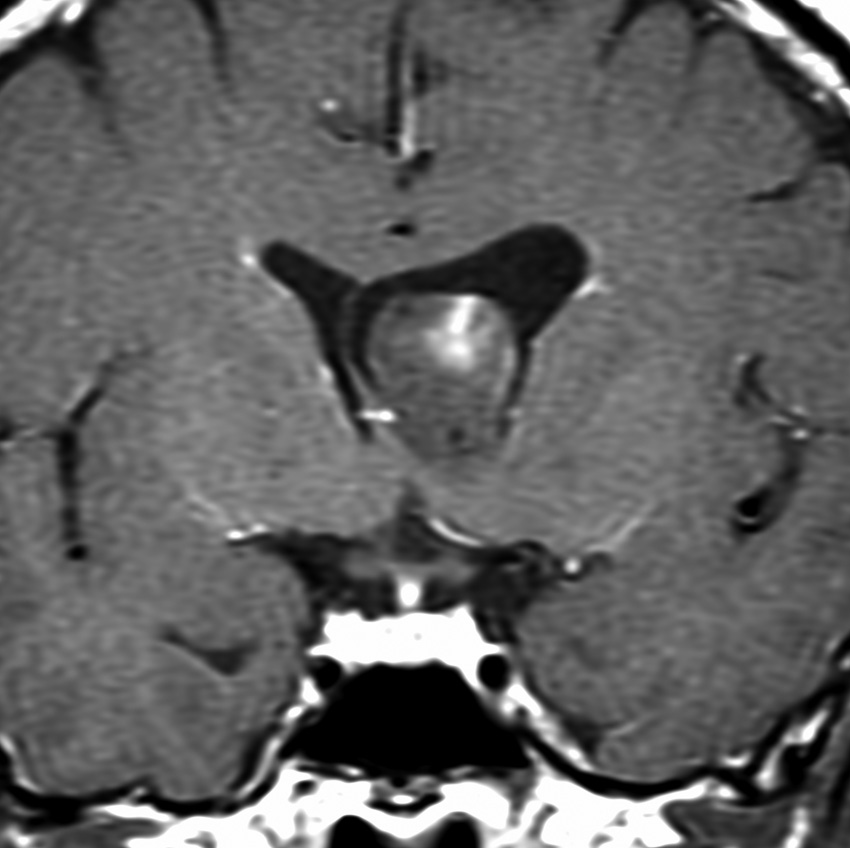

よくみつかる典型的な例です

中年男性に偶然発見された15mmくらいの上衣下腫です。側脳室前角の壁にピッタリくっつくようにキノコのように生えています。下の2枚はガドリニウム造影ですが増強されないのが特徴です。この点で中枢性神経細胞腫 central neurocytomaと区別できます。中枢性神経細胞腫はゆっくりですが大きくなる腫瘍です。でもこのような上衣下腫は大きくなるのはとてもまれです。小さいし水頭症にもならないので,なにも治療しないでほっておきます。間違っても開頭手術などしません。